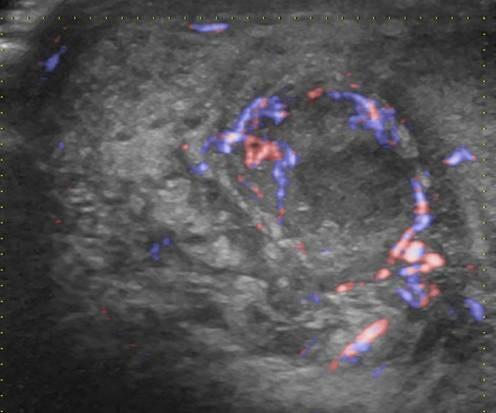

Viêm mào tinh hoàn

» Thông tin: Nam giới – 39 tuổi.

» Lâm sàng: Sưng đau vùng bìu.

# Viêm mào tinh hoàn apxe hóa.